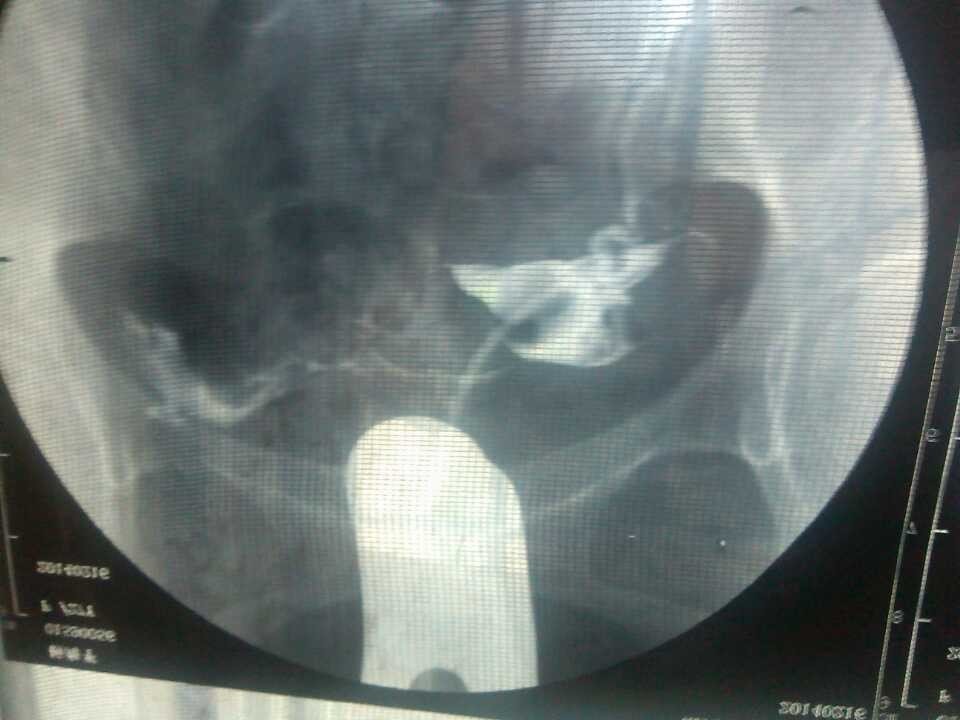

不孕 造影单子帮忙看看 点击展开 匿名用户 2014-04-10 08:51 为您推荐: 其他回答 病情分析: 你好,应该是输卵管堵塞引起的。 指导意见: 可以考虑腹腔镜手术来治疗,术后注意不可过早恢复同房,及时复查。 独水凡_xjeq 2014-04-10 10:34 相关问题 医生你们好帮忙看看我这个造影单子有木有问题 因为我备孕一年 请问医生,不孕单子上这种病情应该怎么办呢?需要手术吗? 谁帮忙看看我下面问题补充里面的检查结果?看看我能不能怀孕??有没有不孕症??